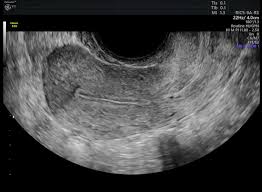

Sometimes cysts on an ultrasound can be mistaken for endometriosis, says dr. It is unclear what causes ovarian cancer, but risk factors include a family history of the condition and mutations in certain genes. There is evidence to suggest that endometriosis may slightly increase a woman's risk of developing this form of cancer. Ovarian cancer is a tumor that forms on one or both of the glands that store eggs in the female reproductive system. I am 42 years old, and have been experiencing perimenopausal symptoms for about 4 years.

The fact that endometriosis can mimic the symptoms of a urinary track infection (also known as a bladder infection) can sometimes trip doctors up a bit. The main difference is, while it can be a serious condition, endometriosis is not deadly or fatal. Many women are told that they. Ovarian cancer can indeed be mistaken for endometriosis. The symptoms for ovarian cancer and endometriosis are much the same so i am worried and confused. However, this does not explain other cancer risk among women with endometriosis. They share some things in common, such as causing cells. Although ovarian cancer occurs at higher rates in women with endometriosis, the overall lifetime risk is low to begin with. Ovarian cancer is a tumor that forms on one or both of the glands that store eggs in the female reproductive system. But even with those cancer types, the risk is still lower than 1%. But if endometriosis patients have abdominal bloating or fullness, changes in bladder or bowel habits or abnormal uterine bleeding, they should consult with their gynecologists. shih adds that abdominal sonography and a ca125 blood test, which measures the cancer antigen in one's blood, can also determine a patient's risk for ovarian cancer. Like with bladder infections, endometriosis can cause painful urination, so these symptoms can. However, endometriomas can sometimes pose an even greater diagnostic challenge, as they can be mistaken for functional ovarian cysts which grow each month as part of a woman's normal monthly ovulatory cycle.